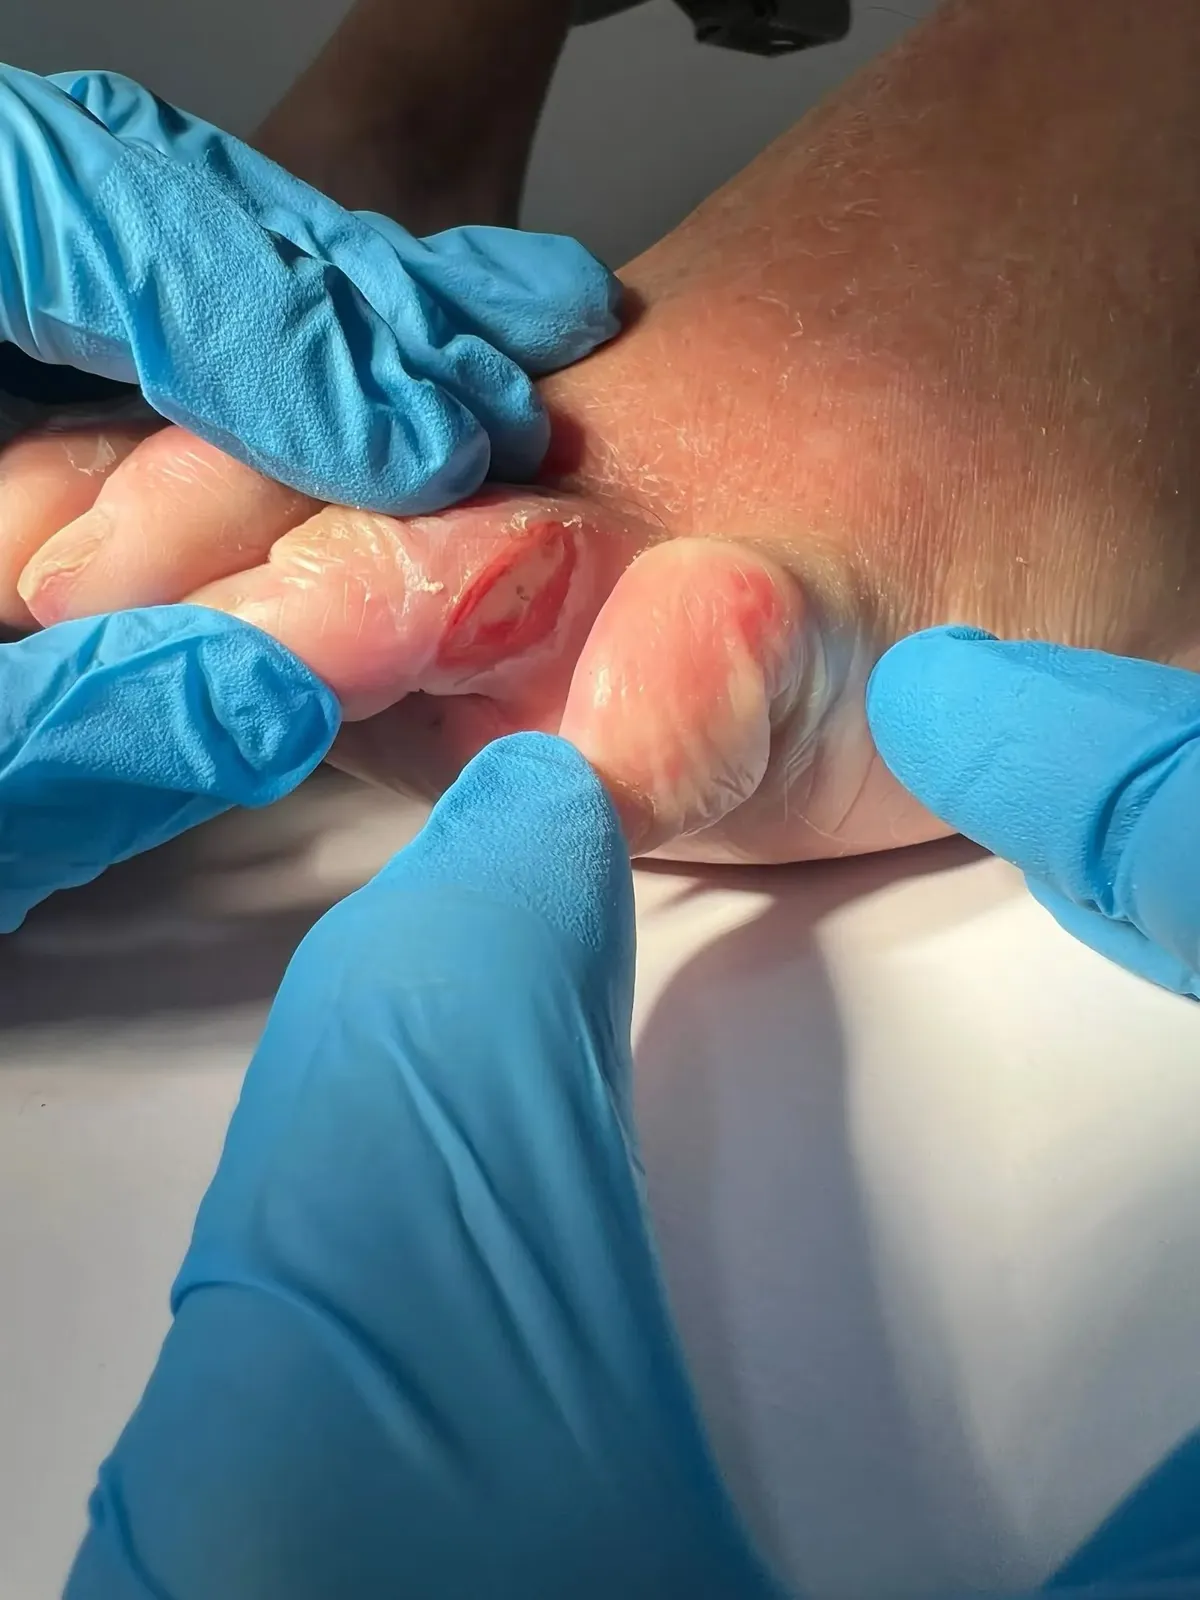

- Piel blanquecina o macerada en los espacios interdigitales

- Pequeñas grietas o fisuras que pueden llegar a doler

Es la forma más frecuente. Afecta a los espacios entre los dedos, con picor entre los dedos del pie, maceración y fisuras. Lo más habitual es que comience entre el cuarto y quinto dedo, donde el espacio es más estrecho y la humedad se acumula con facilidad.